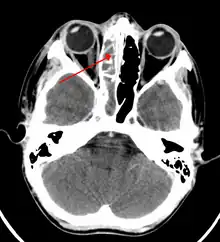

The proximity of the brain to the sinuses makes the most dangerous complication of sinusitis, particularly involving the frontal and sphenoid sinuses, infection of the brain by the invasion of anaerobic bacteria through the bones or blood vessels. Abscesses, meningitis, and other life-threatening conditions may result. In extreme cases, the patient may experience mild personality changes, headache, altered consciousness, visual problems, seizures, coma, and possibly death.[16]

Sinus infection can spread through anastomosing veins or by direct extension to close structures. Orbital complications were categorized by Chandler et al. into five stages according to their severity (see table).[26] Contiguous spread to the orbit may result in periorbital cellulitis, subperiosteal abscess, orbital cellulitis, and abscess. Orbital cellulitis can complicate acute ethmoiditis if anterior and posterior ethmoidal veins thrombophlebitis enables the spread of the infection to the lateral or orbital side of the ethmoid labyrinth. Sinusitis may extend to the central nervous system, where it may cause cavernous sinus thrombosis, retrograde meningitis, and epidural, subdural, and brain abscesses.[27] Orbital symptoms frequently precede intracranial spread of the infection . Other complications include sinobronchitis, maxillary osteomyelitis, and frontal bone osteomyelitis.[28][29][30][31] Osteomyelitis of the frontal bone often originates from a spreading thrombophlebitis. A periostitis of the frontal sinus causes an osteitis and a periostitis of the outer membrane, which produces a tender, puffy swelling of the forehead.

The diagnosis of these complications can be assisted by noting local tenderness and dull pain, and can be confirmed by CT and nuclear isotope scanning. The most common microbial causes are anaerobic bacteria and S. aureus. Treatment includes performing surgical drainage and administration of antimicrobial therapy. Surgical debridement is rarely required after an extended course of parenteral antimicrobial therapy.[32] Chronic sinus infections may lead to mouth breathing, which can result in mouth dryness and an increased risk of gingivitis. Decongestants may also cause mouth dryness.[33]